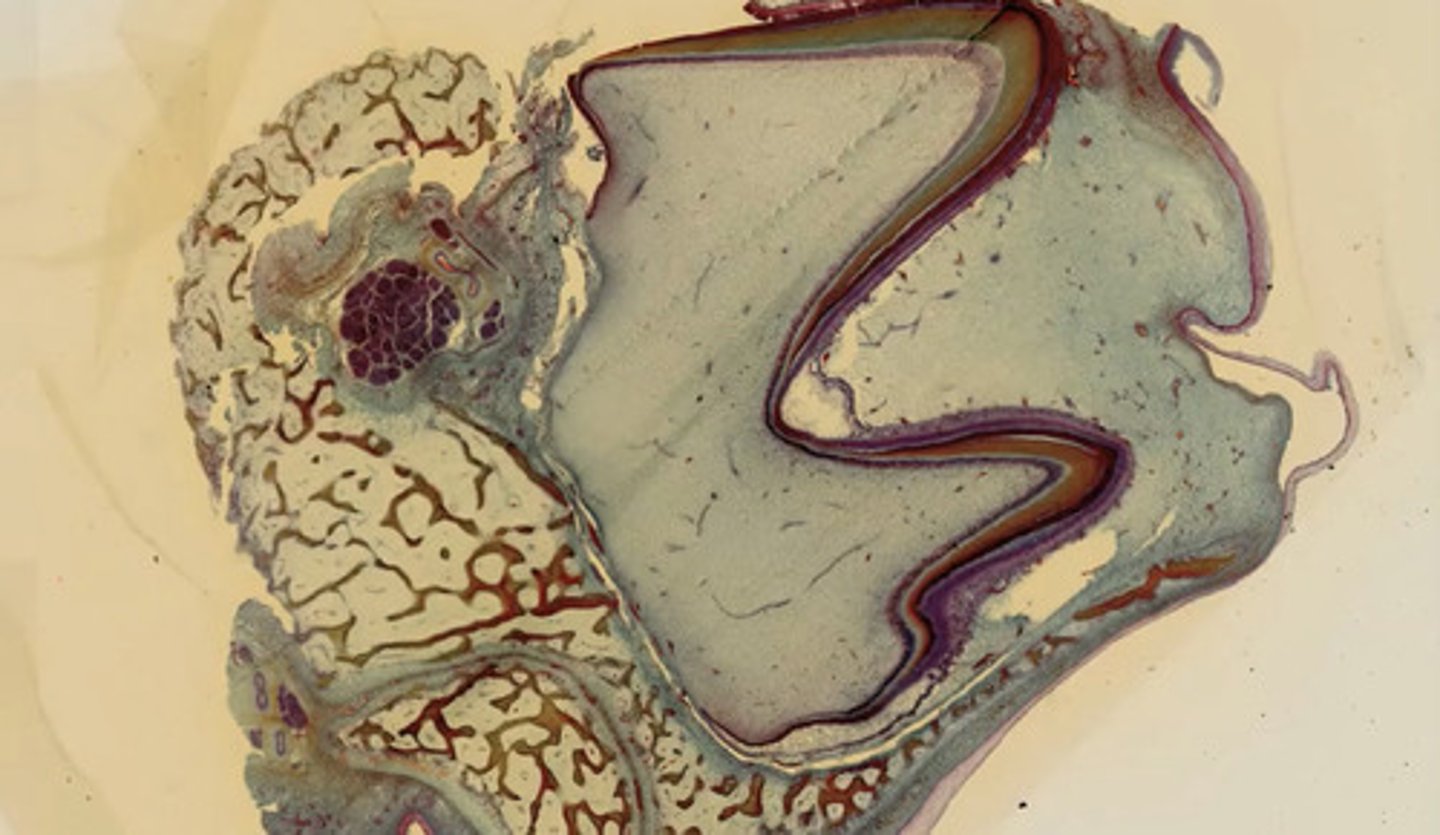

Ząb dojrzały (met. Mallory)

Ząb rozwojowy (met. Mallory)

Ząb dojrzały in situ (met. Mallory)